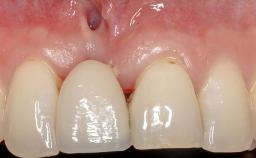

This case demonstrates that a connective-tissue graft in combination with a coronally positioned graft is an effective method of treating cases with peri-implant mucositis and an abutment-level sinus abscess. A 42-year-old man presented with a swelling adjacent to an implant crown at site 21. The swelling had been present for approximately three weeks and was constrained to the buccal and palatal gingival aspects of the implant. A discharge was noted on finger pressure, with localized gingival recession present on the mid- and distolabial aspects of the crown.

Soft Tissue Grafting Staged